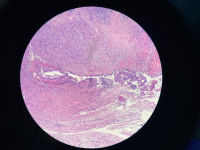

卵巢非典型内膜异位?

性别

女

年龄

49

临床诊断

子宫肌瘤

一般病史

无

标本名称

全子宫双附件

大体所见

附件未见特殊

病灶就这些,请教诊断

图2

像子宫内膜异位